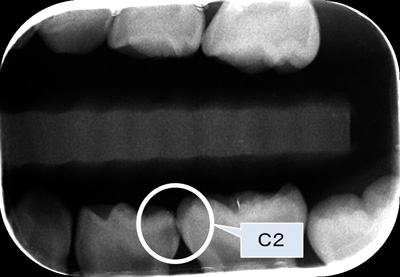

C2とは

C2とは、象牙質(エナメル質の内側にあり、神経細胞が延びてきている組織)に移行した状態で、痛みを伴うようになるので、治療の対象となります。

バイトウィング法(咬翼法)でも、エナメル質から象牙質へ移行している状態を診ることができます。